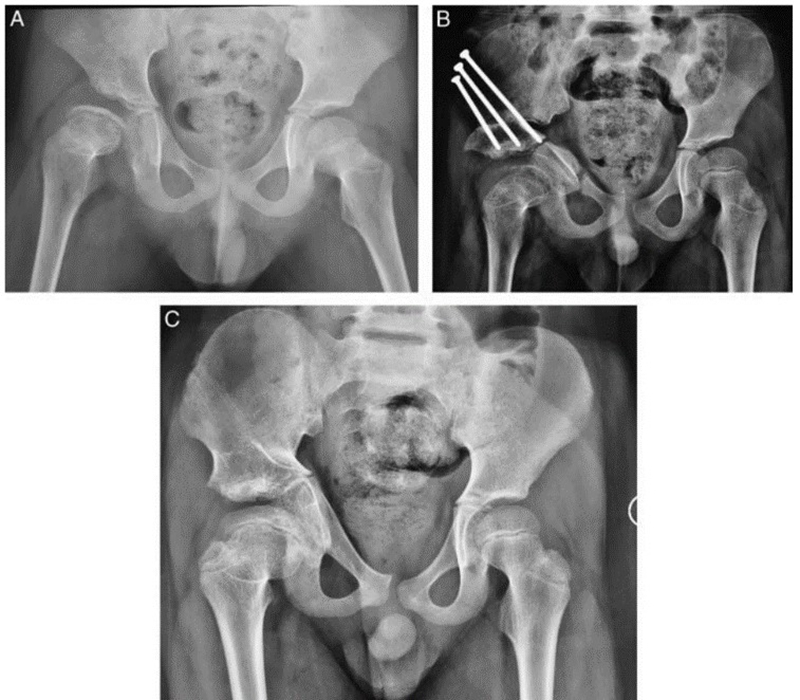

7岁儿童,股骨头缺血坏死,经JST微创骨盆三联截骨后,末次随访提示股骨头形态恢复满意,头臼关系适应好